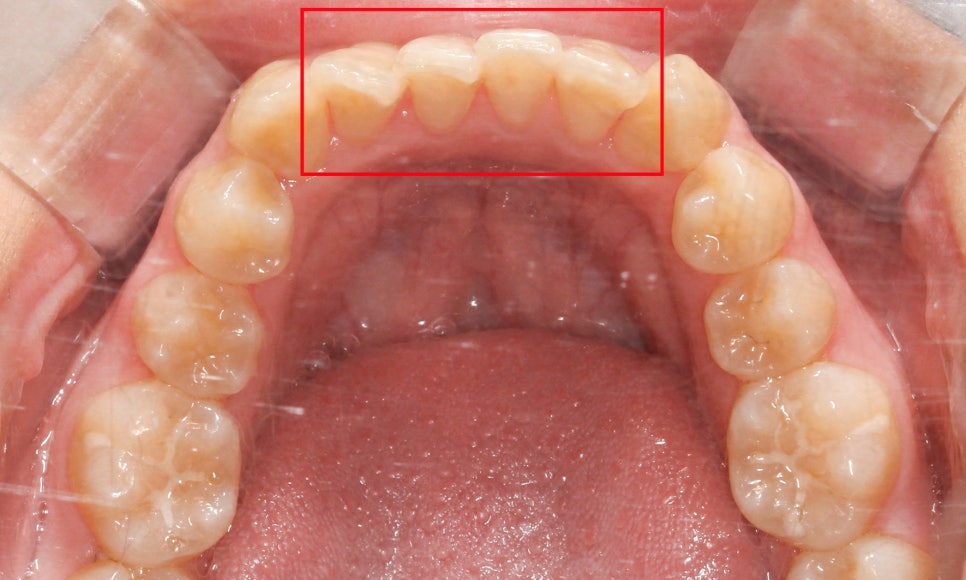

윗니의 안쪽 면을 보면

작은 앞니(측절치)의 크기가

주변 치아보다 확실히 작은 모습인데요,

아랫니를 보시면

왜소치가 아님에도 치아 끝이

톱니처럼 울퉁불퉁한 것을 확인할 수 있습니다!